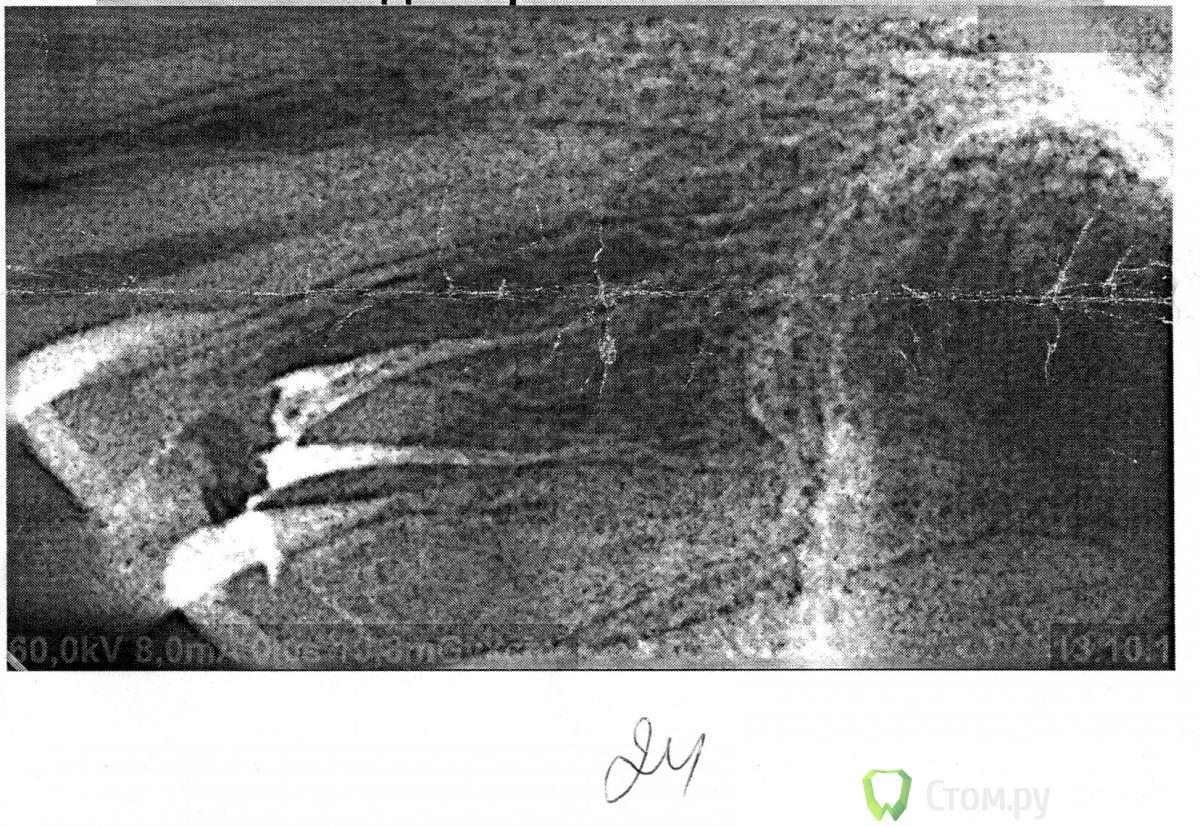

Avlaid Опубликовано 15 ноября, 2011 Поделиться Опубликовано 15 ноября, 2011 Месяц назад удалили зубной нерв на 24 зубе из-за глубокого кариеса, хотя пульпита еще не было. Боль при кусании была где-то недели две, ну это вроде как стандартно. Но примерно в тоже время, когда такие боли закончились, появилась боль от холодной воды (даже комнатной температуры) в десне над эти зубом, причем вода обязательно должна попадать в это место, т.е. с внешней стороны челюсти. Т.е. полоскать рот я не могу. А также боли на улице от ветра в сторону лица. В то же время, десна вроде как стала немного тоньше, легко прощупывается кость корня зуба (как мне кажется), при надавливании туда слегка неприятные ощущения (без боли). Пару дней назад сходил к стоматологу. Продула холодным воздухом каждый зуб, закрывая остальные, а также десну, - болей нет. Продула десну - боли есть. Она разводит руками говорит, что зуб болеть не может, воспаления тоже быть не может, так как до лечения воспаления не было. Ты, говорит, первый такой с такими жалобами. Отправила на лазер на 3-4 сеанса. Прошел пока два из них, никакого улучшения. P.S.: снимок в первый день лечения после удаления нерва и закладывания временной пломбы прилагаю. Последующих снимков не делалось. Ссылка на комментарий

Avlaid Опубликовано 27 февраля, 2012 Автор Поделиться Опубликовано 27 февраля, 2012 (изменено) Скорее всего, пульпит в 25. А каналы 24 надо переделать...Много врачей смотрели снимок но никто про переделку каналов не говорил Я смог таки сфоткать рентген, выкладываю на всякий случай как наиболее свежий снимок http://img853.imageshack.us/img853/1836/19432142.jpg Изменено 27 февраля, 2012 пользователем Avlaid Ссылка на комментарий